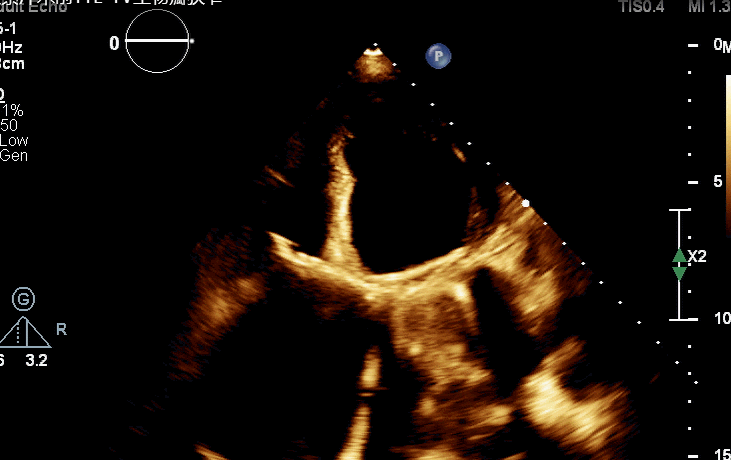

术前TTE-TV生物瓣狭窄

术后三维超声同时显示MV机械瓣及新的TV生物瓣